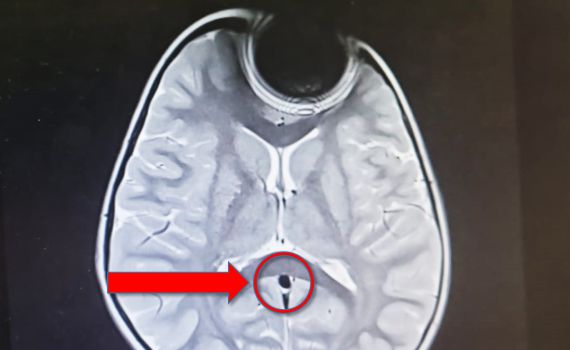

בבדיקות הדימות שבוצעו, נמצאו אינדיקציות להימצאות של גורם זר באפה של הפעוטה -סוללה קטנה- מה שהוביל לתגובות שונות של המערכת הגופנית של הילדה הקטנה אשר גרמו לאותם סימפטומים, משנמצא מקור הבעיה, הוצאה הסוללה מאפה של המטופלת על ידי צוות אא"ג, כשהיא תחת טשטוש. לאחר מכן היא נותרה להשגחה ולבסוף שוחררה לביתה כשהיא חשה בטוב.